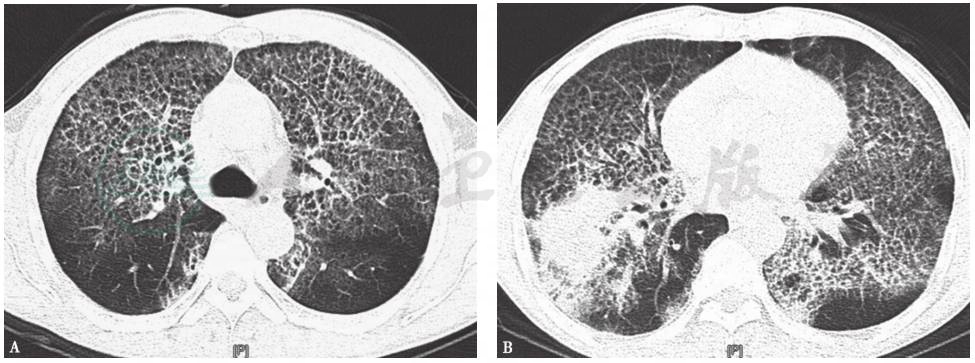

术后,给予减轻肺水肿(呋塞米)、吸氧、抗感染、舒张支气管、祛痰及无创机械通气等治疗,患者感胸闷气促等症状明显缓解。1个月后复查CT提示双肺病灶较前吸收,右下肺大片实变影较前缩小(图6)。患者病情好转出院后,采取吸入GM-CSF治疗,定期随访,状态良好。

图6 入院1个月后胸部CT表现